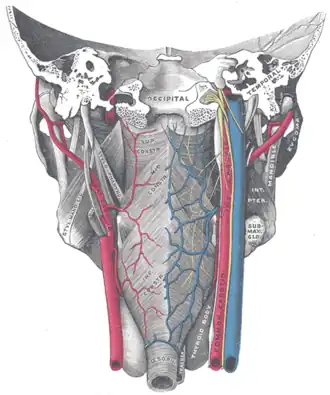

Muscles of the pharynx, viewed from behind, together with the associated vessels and nerves. (Pharyngeal plexus visible but not labeled.) | |

The pharyngeal plexus is a nerve plexus located upon the outer surface of the pharynx. It contains a motor component (derived from the vagus nerve (cranial nerve X)), a sensory component (derived from the glossopharyngeal nerve (cranial nerve IX)), and sympathetic component (derived from the superior cervical ganglion).[1]

The plexus provides motor innervation to most muscles of the soft palate (all but the tensor veli palatini muscle) and most muscles of the pharynx (all but the stylopharyngeus muscle).[1] The larynx meanwhile receives motor innervation from the vagus nerve (CN X) via its external branch of the superior laryngeal nerve and its recurrent laryngeal nerve, and not through the pharyngeal plexus.

The pharyngeal plexus occurs upon the outer surface of the pharynx - especially superficial to the middle pharyngeal constrictor muscle.[1]

En route to their target tissues, outgoing fibres from the pharyngeal plexus at first either ascend upon the superior pharyngeal constrictor muscle or descend upon the inferior pharyngeal constrictor muscle, then ramify within the pharyngeal muscular layer and mucous membrane.[1]

The pharyngeal plexus, with fibers from CN IX, CN X, and cranial part of CN XI, innervates all the muscles of the pharynx (except stylopharyngeus, which is innervated directly by a branch of CN IX).

This includes the following muscles: palatopharyngeus, palatoglossus, musculus uvulae, the pharyngeal constrictors, salpingopharyngeus plus others.

The pharyngeal plexus provides sensory innervation to most of the pharynx;[1] it provides sensory innervation to the oropharynx and laryngopharynx from CN IX and CN X. (The nasopharynx above the pharyngotympanic tube and the torus tubarius is innervated by CN V2).